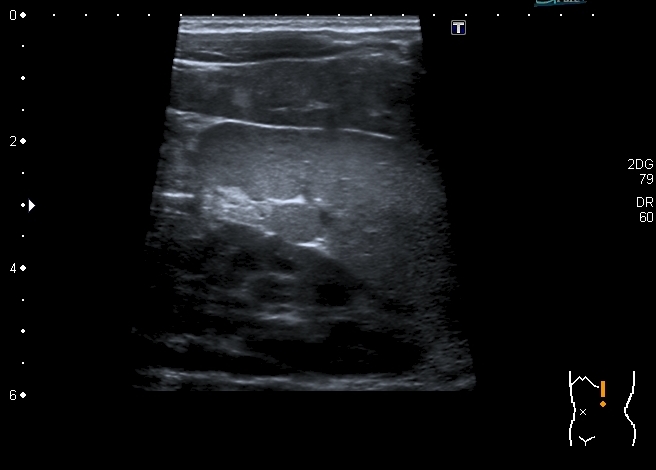

Ребёнок 2.5 месяцев, доставлен в связи с выявленным при очередном осмотре увеличением печени.

При УЗИ: печень резко увеличена, больше за счёт левой доли

Паренхима печени -гиперэхогенная , неоднородная, практически полностью замещена нодулярными образованиями, некоторые из них с "гало" и кальцификацией